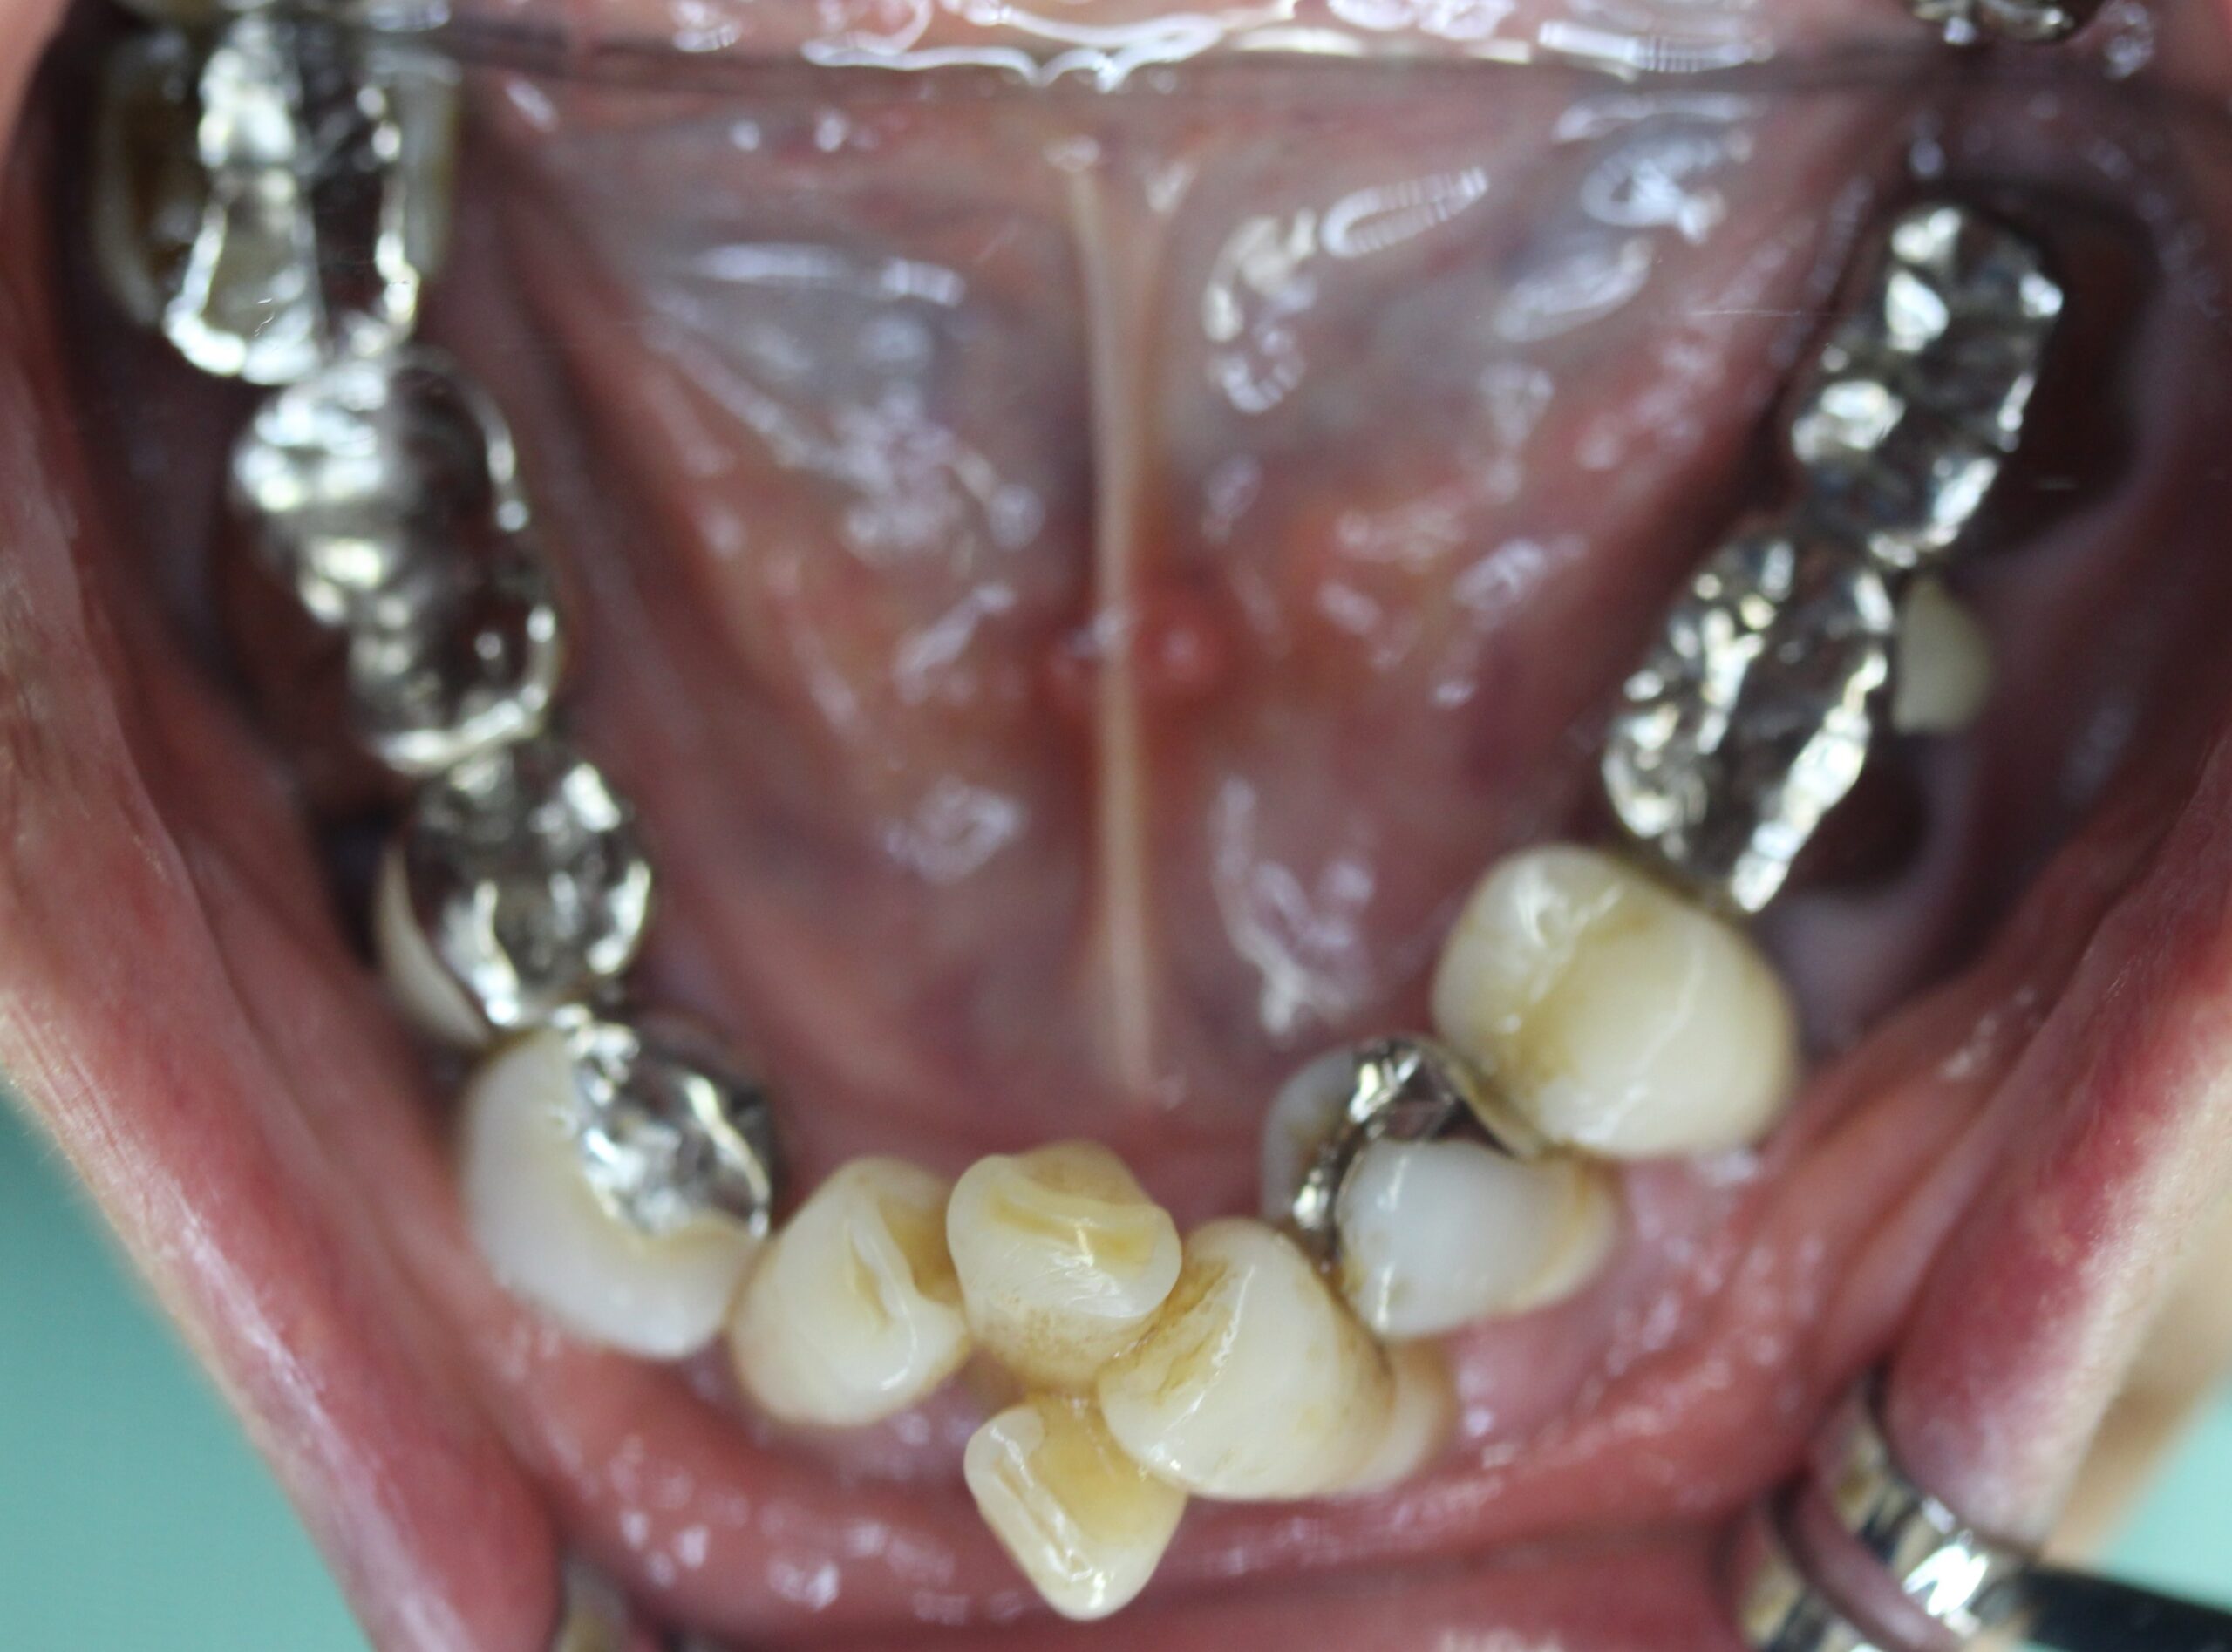

上顎はコーヌステレスコープ、下顎はレジリエンツテレスコープにて治療を行なった。

【治療前】